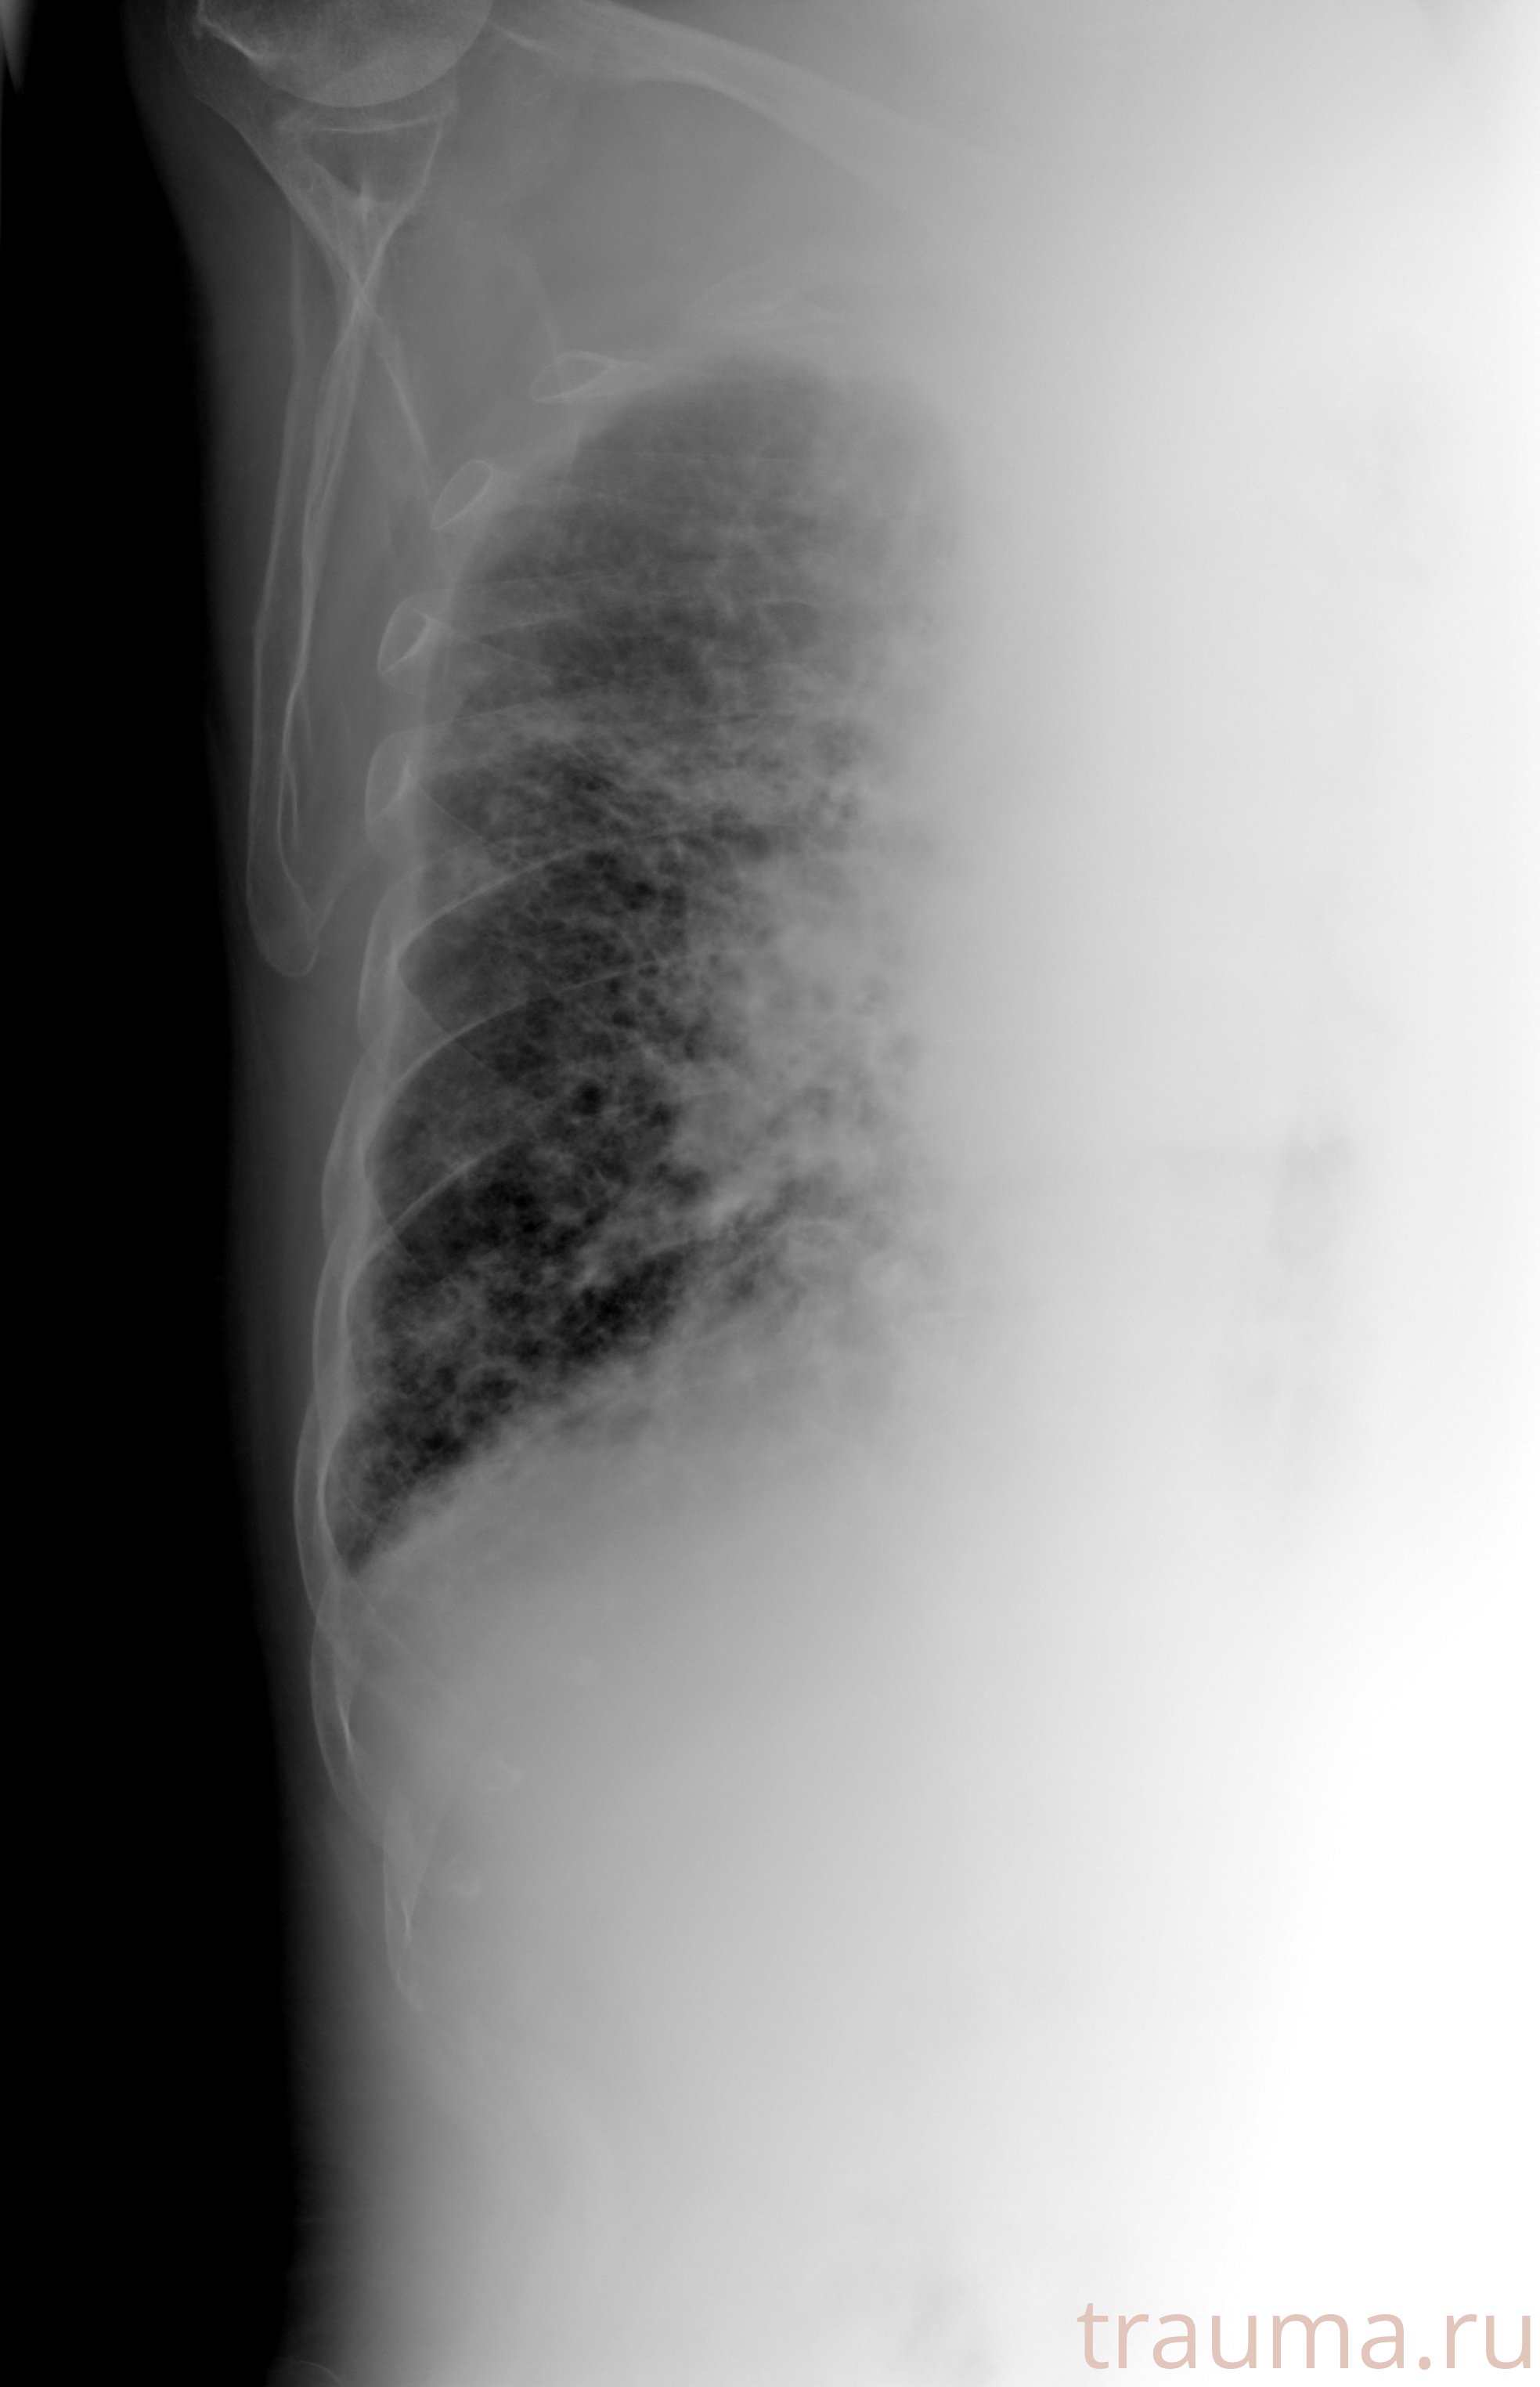

Рентген на дому: по вашему адресу приезжает врач-рентгенолог, травматолог-ортопед с мобильным рентгеновским аппаратом, проводит диагностику травмы или заболевания, делает необходимые рентгенограммы, дает рекомендации по дальнейшему лечению. Получить качественные снимки в домашних условиях возможно благодаря уникальной методике, разработанной МосРентген Центром для института  Склифосовского

при переломе шейки бедра и пневмонии от компании МосРентген Центр - партнера Института имени Склифосовского